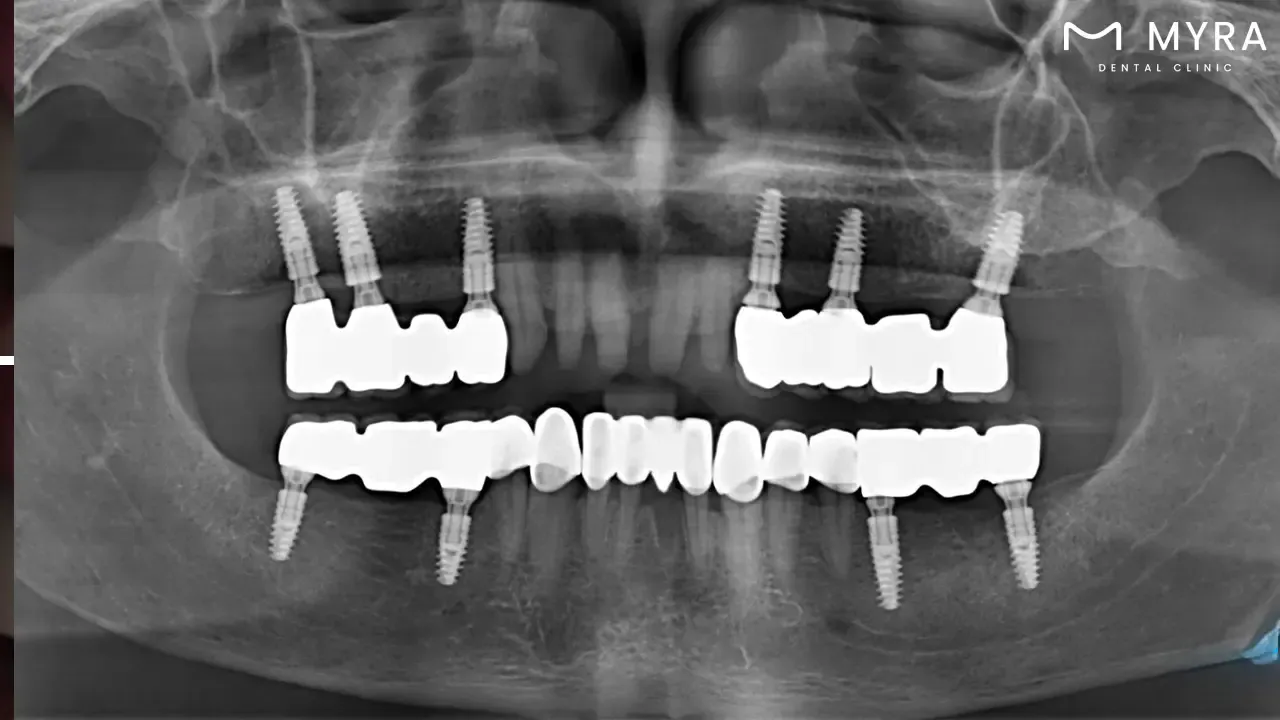

It is common to practise using a long-term solution that replicates the original teeth in terms of how they seem, how they feel, and how they function in reconstructing a patient's smile after tooth loss or damage. It is custom-made to blend in with the patient's natural teeth, resulting in a sleek and aesthetically pleasing finish. They provide a solution that is extremely long-lasting and long-lasting overall, and with proper dental hygiene, they last for decades. What is a dental implant? Dental implants are artificial tooth roots that are surgically implanted into the jawbone to provide a strong foundation for replacement teeth. They are constructed out of components compatible with the human body, such as titanium, which undergoes a process known as osseointegration, in which it joins forces with the bone over time.

People who have lost teeth as a result of an accident, tooth rot, or any number of other factors frequently opt for dental implants since they are widespread and effective. They provide a solution that is both more permanent and more pleasant than the more conventional dentures or bridges because they seem and function much like real teeth.

It is essential to keep in mind that dental implants are not a treatment option for everyone who benefits from them. The patient must have sufficient bone density as well as adequate oral health for implantation to be successful. The procedure is typically broken up into several stages, and it takes the gums several months to heal before the replacement teeth are attached to the implants.

The success of dental implants is directly proportional to the quality of care and upkeep that they receive. Dental implants need patients to maintain a high level of oral cleanliness and to undergo routine dental examinations.